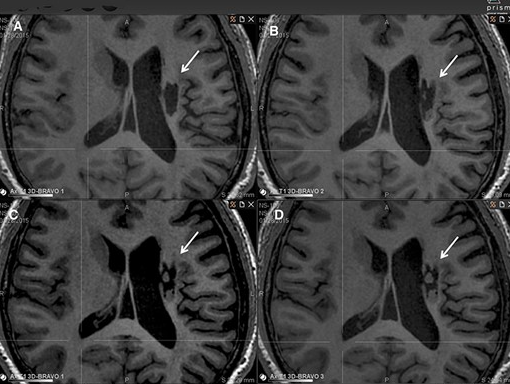

神經(jīng)干細(xì)胞移植治療24個月后,患者運(yùn)動能力和日常生活能力改善,神經(jīng)受損程度持續(xù)降低并且影像學(xué)也持續(xù)改善。

影像學(xué)檢查:在 6 個月的隨訪中,所有 9 名受試者均觀察到新組織,源自腦軟化梗塞腔。該腔內(nèi)組織外觀具有以下特征:短期活力(術(shù)后第一次 MRI 與基線相比的組織外觀)—9 例中有 9 例;生長(術(shù)后至少兩次 MRI 中新組織增加)—6 例中有 6 例;穩(wěn)定(術(shù)后至少兩次 MRI 中新組織沒有變化;即生長平臺期,最長為 24 個月)—6 例中有 5 例;無法獲得 24 個月后的長期活力。

(A)基線時,(B) 6 個月隨訪時,(C) 12 個月隨訪時,(D) 24 個月隨訪時。